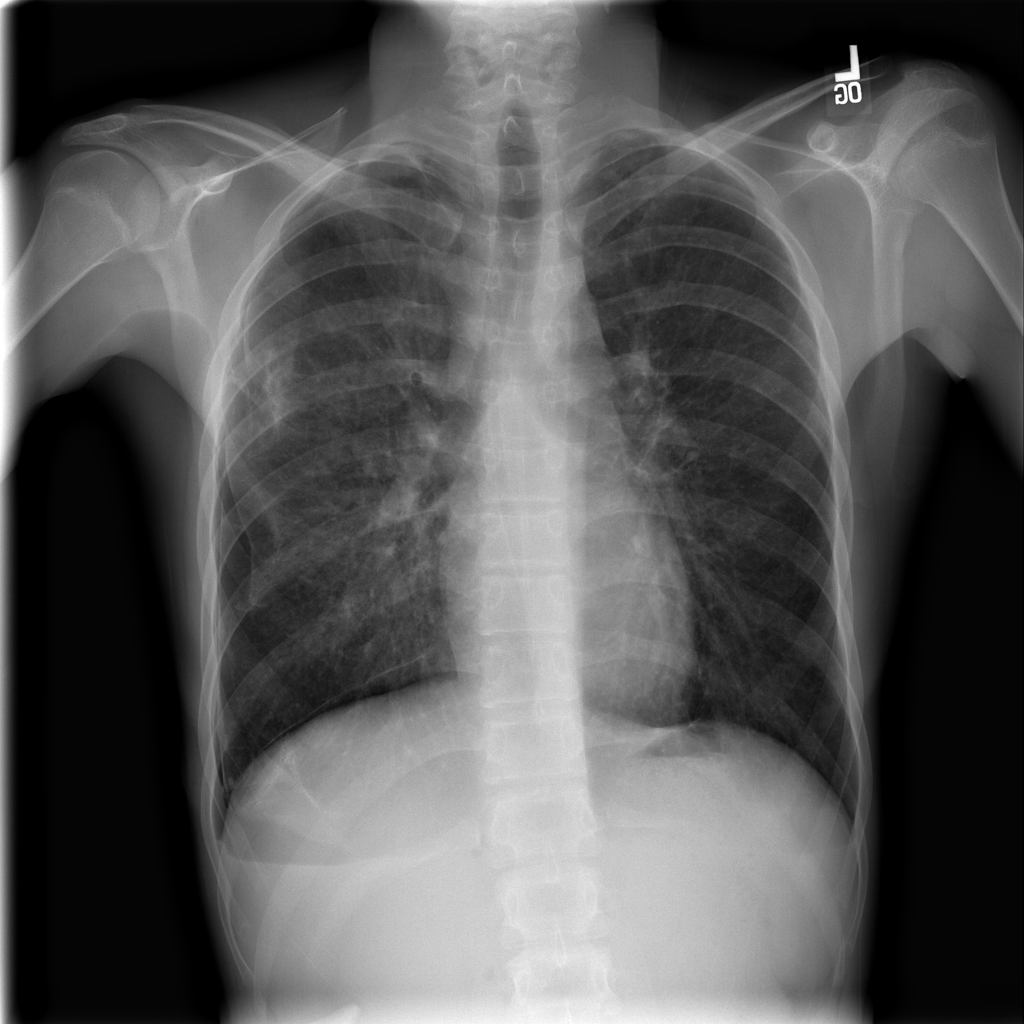

Showing up to 90 reference images for Pneumothorax.

PAT-4639 · IMG-013Pneumothorax

PAT-4639 · IMG-013

AP